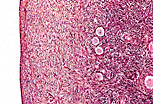

大体观察苏木精-伊红-藏红花(HES)染色的淋巴结切片,可区分两个区域:外周的皮质区富含淋巴细胞,染色较深(嗜碱性);中央的髓质区染色较浅。 |

皮质区充满淋巴细胞,掩盖了网状组织构成的支架,仅在髓质区可观察到该支架:髓质区有形状不规则的透亮区(髓窦),分隔着染色深、细胞密集的髓索。髓索中主要包含浆细胞及其前体细胞,淋巴液在髓窦中循环。

起自被膜和门部的结缔组织小梁穿过髓质区,为淋巴结的血管提供支撑。 |